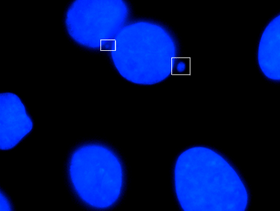

Micronuclei visible in boxes

Micronucleus is the name given to the small nucleus that forms whenever a chromosome or a fragment of a chromosome is not incorporated into one of the daughter nuclei during cell division. It usually is a sign of genotoxic events and chromosomal instability. Micronuclei are commonly seen in cancerous cells and may indicate genomic damage events that can increase the risk of developmental or degenerative diseases.[1] Micronuclei form during anaphase from lagging acentric chromosome or chromatid fragments caused by incorrectly repaired or unrepaired DNA breaks or by nondisjunction of chromosomes. This incorrect segregation of chromosomes may result from hypomethylation of repeat sequences present in pericentromeric DNA, irregularities in kinetochore proteins or their assembly, dysfunctional spindle apparatus, or flawed anaphase checkpoint genes.[2] Many micronucleus assays have been developed to test for the presence of these structures and determine their frequency in cells exposed to certain chemicals or subjected to stressful conditions.